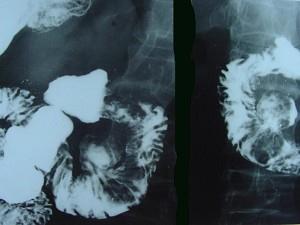

问题 男,55岁,中上腹隐痛多年,剑突下压痛,影像检查如图,最可能的诊断是 ( )

选项 A、十二指肠重复畸形 B、十二指肠穿孔 C、十二指肠憩室 D、十二指肠癌 E、十二肠溃疡

答案 C